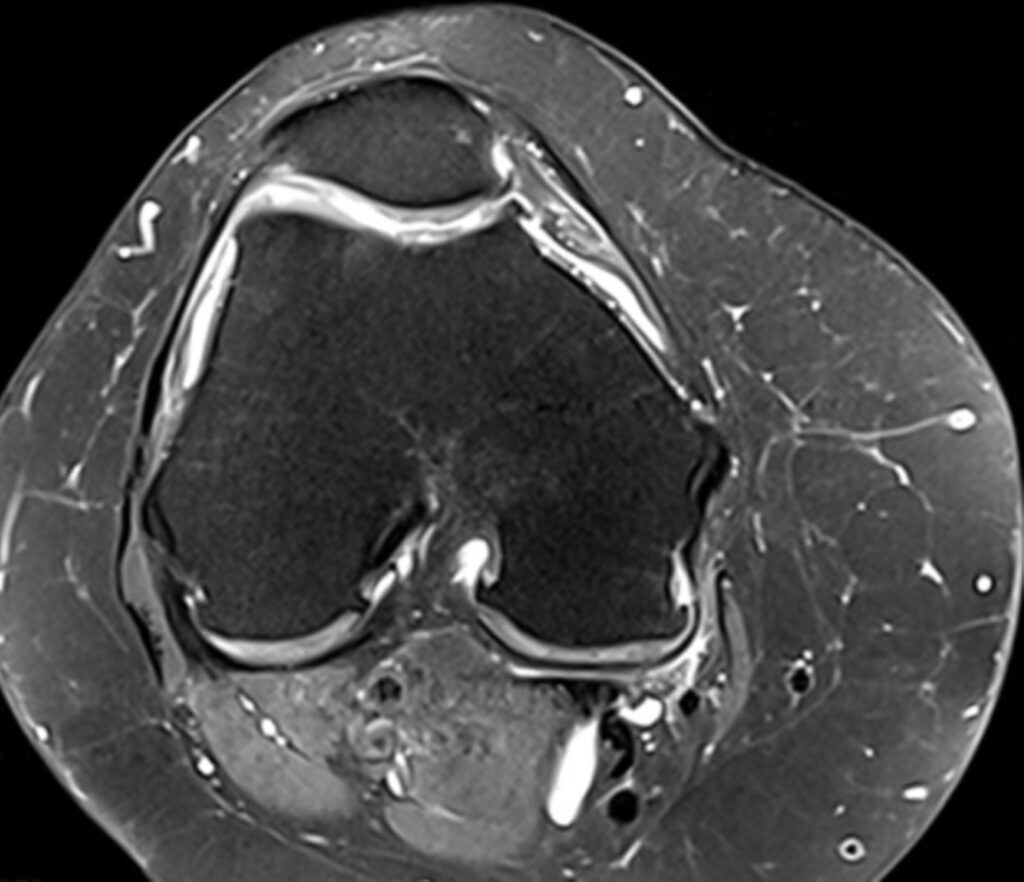

MRT Knie

Der Meniskusriss ist eine typische Sportverletzung. Die Lokalisation, die Größe als auch die Form des Risses lassen sich anhand der Aufnahmen analysieren. Diese sind für die anschließende Therapie von großer Bedeutung

Kniearthrose lässt sich im Rahmen einer MRT-Untersuchung ebenfalls genauer analysieren. Sind sogenannte „weiße Stellen“ im MRT zu erkennen, handelt es sich hierbei möglicherweise um Zeichen einer Flüssigkeitsansammlung und könnte ein Hinweis auf ein Knochenmarködem sein.